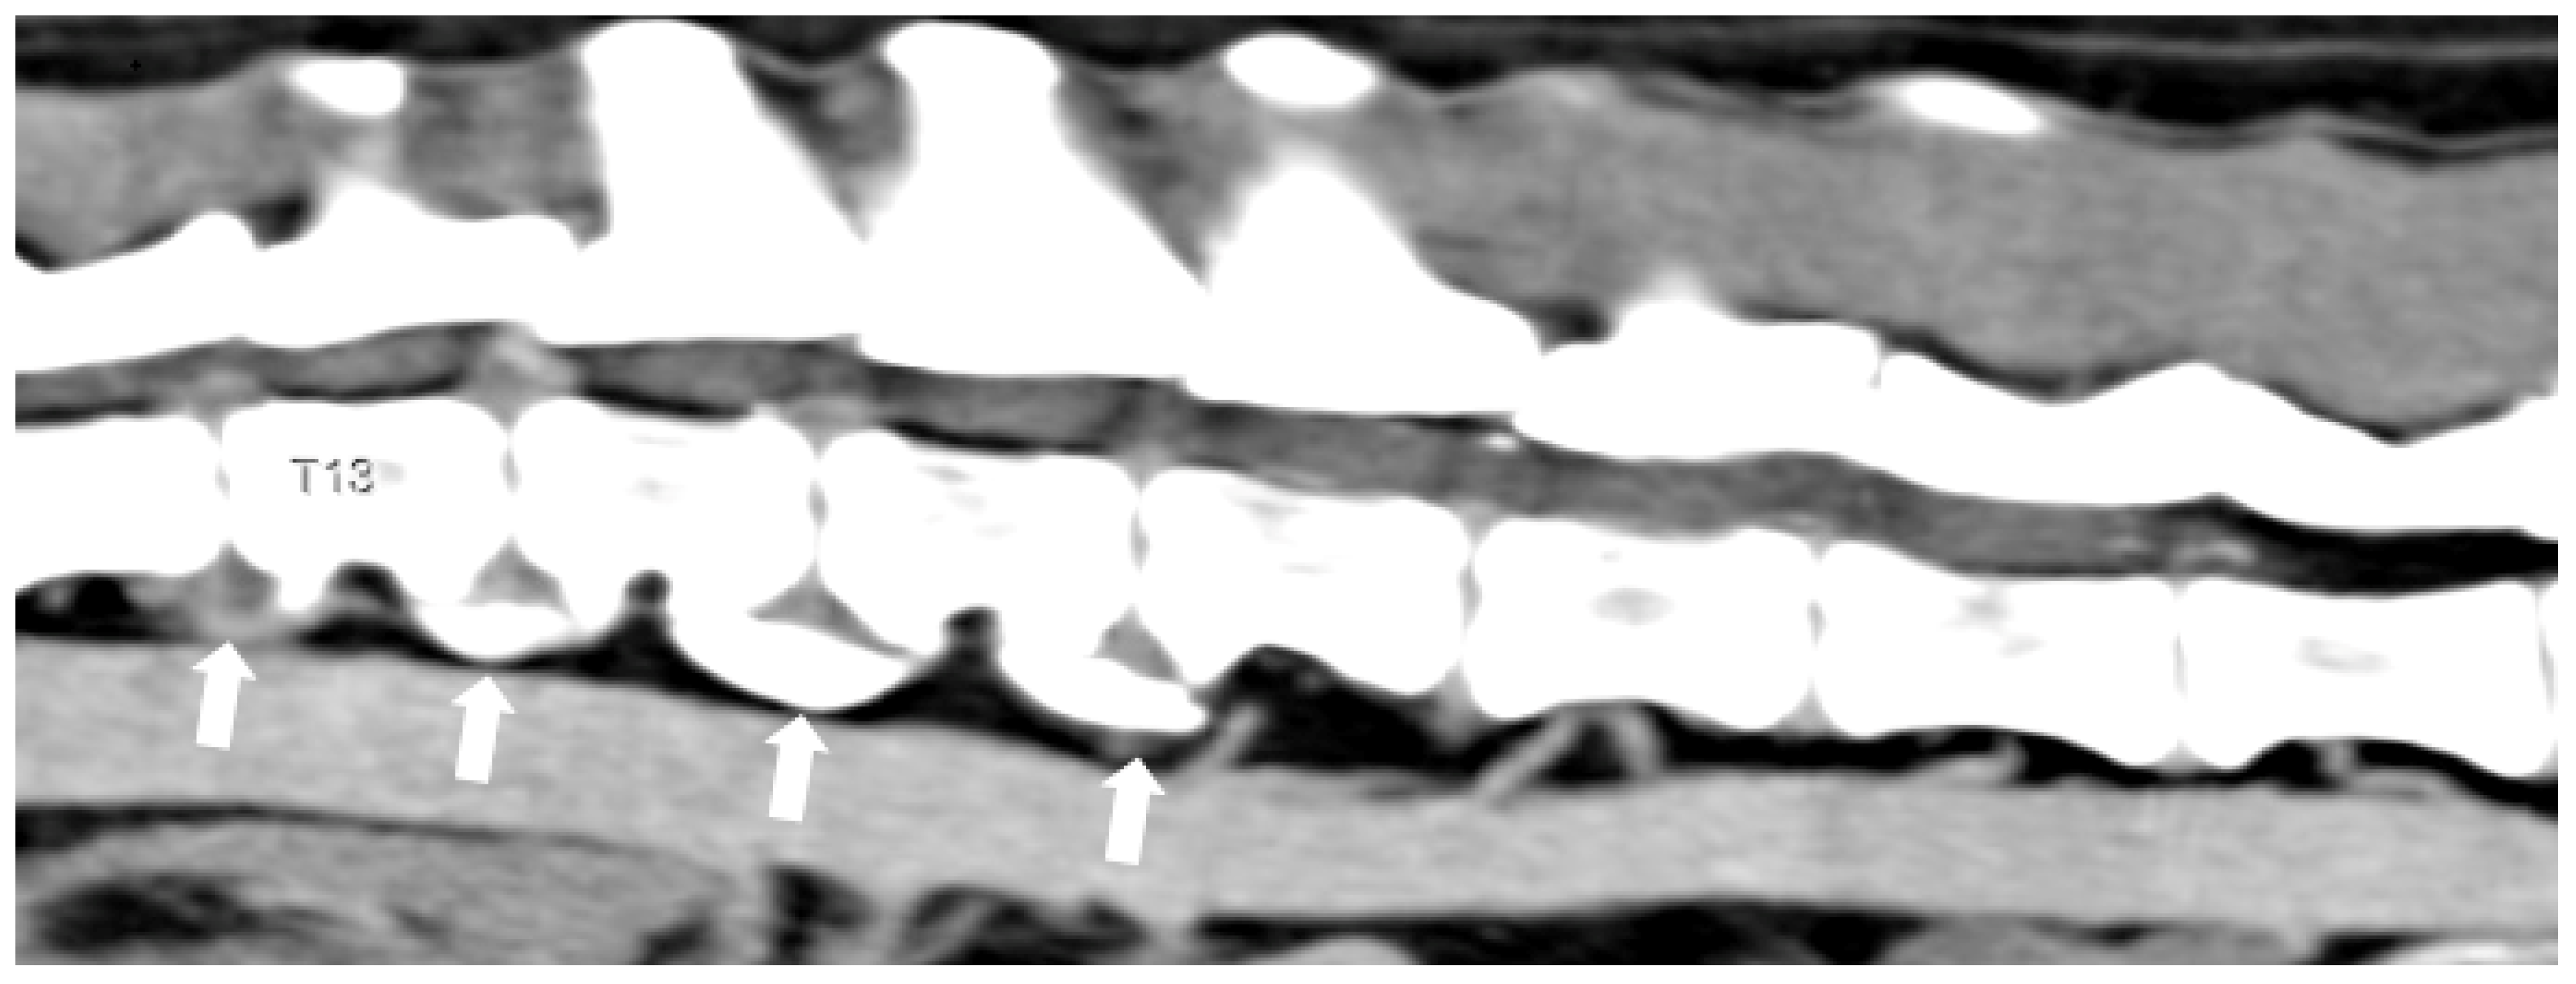

3.1. Intervertebral Disc Disease

- Fenn, J.; Olby, N.J. Canine Spinal Cord Injury Consortium (CANSORT-SCI) Classification of Intervertebral Disc Disease. Front. Vet. Sci. 2020, 7, 579025. [Google Scholar] [CrossRef]

- Hansen, H.J. A Pathologic-Anatomical Interpretation of Disc Degeneration in Dogs. Acta Orthop. Scand. 1951, 20, 280–293. [Google Scholar] [CrossRef]

- Macias, C.; Mckee, W.M.; May, C.; Innes, J.F. Thoracolumbar Disc Disease in Large Dogs: A Study of 99 Cases. J. Small Anim. Pract. 2002, 43, 439–446. [Google Scholar] [CrossRef]

- Bergknut, N.; Smolders, L.A.; Grinwis, G.C.M.; Hagman, R.; Lagerstedt, A.-S.; Hazewinkel, H.A.W.; Tryfonidou, M.A.; Meij, B.P. Intervertebral Disc Degeneration in the Dog. Part 1: Anatomy and Physiology of the Intervertebral Disc and Characteristics of Intervertebral Disc Degeneration. Vet. J. 2013, 195, 282–291. [Google Scholar] [CrossRef]

- Smolders, L.A.; Bergknut, N.; Grinwis, G.C.M.; Hagman, R.; Lagerstedt, A.-S.; Hazewinkel, H.A.W.; Tryfonidou, M.A.; Meij, B.P. Intervertebral Disc Degeneration in the Dog. Part 2: Chondrodystrophic and Non-Chondrodystrophic Breeds. Vet. J. 2013, 195, 292–299. [Google Scholar] [CrossRef]

- Crawford, A.H.; De Decker, S. Clinical Presentation and Outcome of Dogs Treated Medically or Surgically for Thoracolumbar Intervertebral Disc Protrusion. Vet. Rec. 2017, 180, 569. [Google Scholar] [CrossRef] [PubMed]

- Gomes, S.A.; Volk, H.A.; Packer, R.M.; Kenny, P.J.; Beltran, E.; De Decker, S. Clinical and Magnetic Resonance Imaging Characteristics of Thoracolumbar Intervertebral Disk Extrusions and Protrusions in Large Breed Dogs. Vet. Radiol. Ultrasound 2016, 57, 417–426. [Google Scholar] [CrossRef] [PubMed]

- De Decker, S.; Gomes, S.A.; Packer, R.M.; Kenny, P.J.; Beltran, E.; Parzefall, B.; Fenn, J.; Nair, D.; Nye, G.; Volk, H.A. Evaluation of magnetic resonance imaging guidelines for differentiation between thoracolumbar intervertebral disk extrusions and intervertebral disk protrusions in dogs. Vet. Radiol. Ultrasound 2016, 57, 526–533. [Google Scholar] [CrossRef]